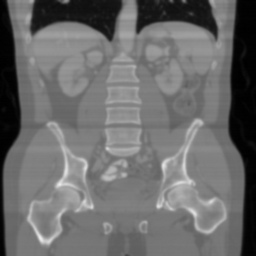

| Ground Truth | Input | DDS-100 [chungdecomposed] | DDS-200 [chungdecomposed] | NERD-P (Ours) |

![]() |

Settings: We largely follow the setup from DiffMBIR [Chung_2023_CVPR] and DDS111https://github.com/hyungjin-chung/DiffusionMBIR[chungdecomposed]. This includes the 2D pre-trained DM and one volume of the testing dataset (which is from the AAPM CT challenge set with eight views222https://www.aapm.org/grandchallenge/lowdosect/). For baselines, we consider DiffMBIR which requires 1000 sampling steps and is 5 times slower than our proposed NERD algorithms, and two versions of DDS: one with 100 sampling iterations (DDS-100) and one with 200 sampling iterations (DDS-200). DDS-100 has approximately the same run-time as NERD-A and NERD-P with , whereas DDS-200 takes twice as long as NERD-A and NERD-P. All methods were run on the same machine: a single RTX5000 GPU machine. For NERD-A, we use , , . For NERD-P, we use , , , . For Adam, we use a step size of with gradient updates, i.e., for the optimization problem in Step 1 of NERD-A and Step 3 of NERD-P. The hyper-parameters were selected based on trying a set of values and then selecting the best ones. Ablation studies are left for future work. The measurement noise level is set to . Our code is online333https://github.com/sjames40/3D_SITCOM.

Convergence results: In Figure 1, we report average PSNR w.r.t. the number of sampling steps. As observed, DDS requires significantly more iterations to improve PSNR compared to NERD-P. Not only does our method converge faster, but it also achieves higher PSNR. Specifically, DDS reaches 39.5 dB after 100 sampling steps and 39.78 dB after 200 steps, while our method achieves 40.68 dB in just 30 steps. Moreover, we observe that DDS shows little improvement in PSNR until the later sampling steps. Notably, our method and DDS-100 require approximately the same wall-clock time on the same machine, despite using only 30 steps compared to DDS’s 100. This is because DDS employs CG updates and avoids backward passes through the pre-trained 2D DM, unlike our method (NERD). We hypothesize that the use of network regularization in our method enables such a substantial reduction in sampling steps while still maintaining high-quality reconstructions.

Main results: In Table 1, we present quantitative results and in Figure 2, we show visualizations in the axial, coronal, and sagittal planes. Our methods consistently outperform the second-best baseline across most views, achieving nearly 1 dB higher PSNR on average. Despite incorporating a few additional input updates to enforce data consistency, our method reaches competitive performance with only 30 sampling steps. Based on the visualizations, we observe that DDS introduces slight artifacts along the horizontal direction, particularly noticeable in the coronal and sagittal views. In contrast, our method produces cleaner reconstructions with fewer artifacts in these orientations.